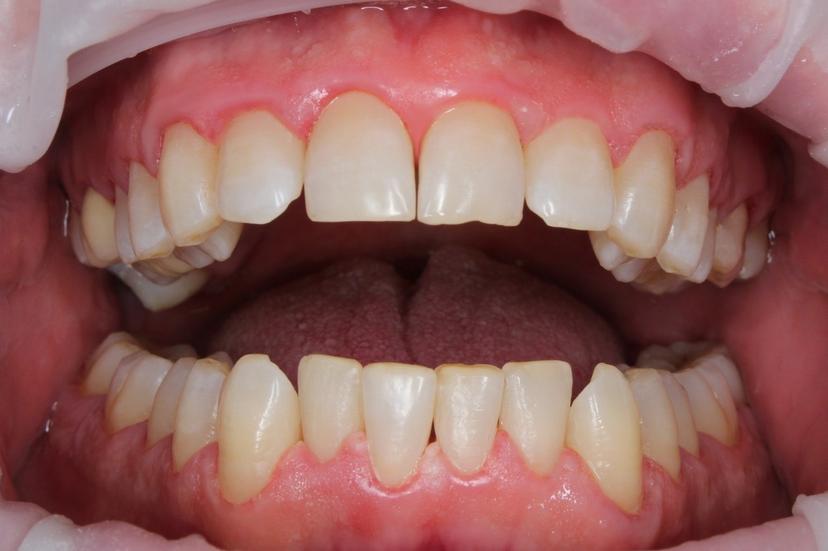

Пациент пришел с жалобами на неприятный запах изо рта и на темный налёт, который не убирается зубной щеткой.

Для снятия зубных отложений мы провели комплексную профилактическую гигиену с применениям ультразвука, AIR FLOW, щетки с пастой.

ДО: Заметны налет, пигментация и твердые зубные отложения, что придает неухоженный вид зубам.

После: Поверхность зубов очищена, восстановлен их естественный цвет, отсутствуют твердые зубные отложения и налет. Зубы выглядят здоровыми и ухоженными, а десны - свежими и более розовыми.